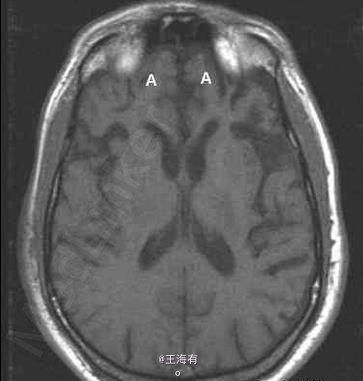

49岁,男,进行性行为改变入院

进行性智能减退,记忆障碍明显

Pick病 处理 此病暂无有效疗法

Pick病是一种罕见的进行性变性疾病,大多累及额叶和颞叶。预后本病预后不良。常在发病1年内迅速转入痴呆